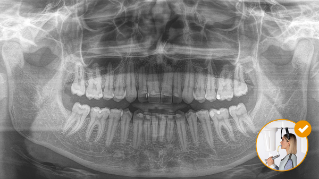

Výsledek: Přesné skeny díky okluznímu skusovému bloku

Správná poloha pacienta s okluzním skusovým blokem ‒ zaručený ideální sklon pro panoramatické snímky

Nesprávná poloha pacienta ‒ pacient je nakloněn dopředu

Nesprávná poloha pacienta ‒ pacient je nakloněn dozadu